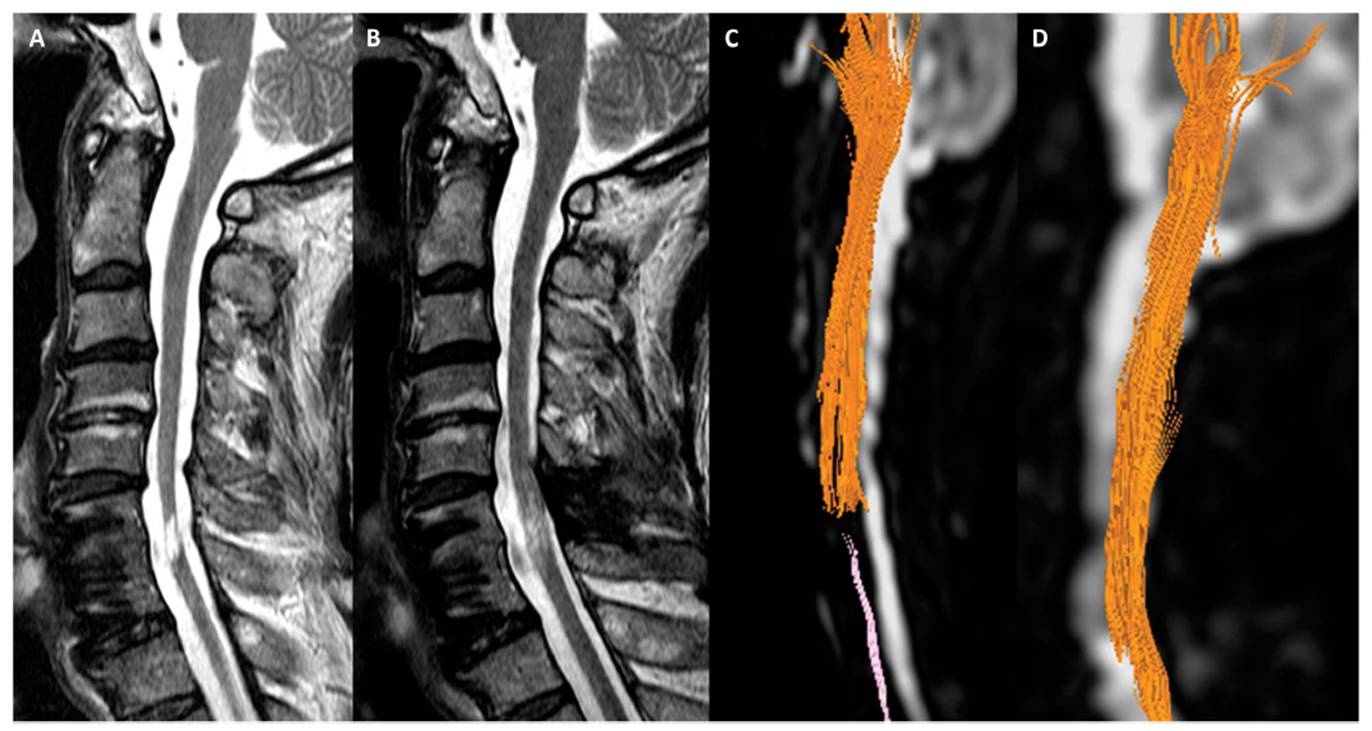

이어 “그러나 줄기세포치료제를 단회 투여했음에도 불구하고 호전된 환자의 척수 MRI 및 DTI 검사 결과 척수손상 부위에서 줄기세포치료 전에는 없던 섬유의 연속성(fibercontinunity)이 확인되는데 이는 줄기세포치료로 인한 신경재생 효과로 판단할 수 있다"고 말했다.

[환자의 MRI와 DTI검사결과다. 줄기세포치료제투여하기 전(A와C)에 비해 투여 후 6개월이 경과한 후(B와 D)에는끊어진 척수신경이 재생되었음을 확인할 수 있다.]